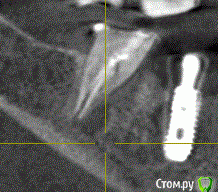

se77777 Опубликовано 10 марта, 2020 Поделиться Опубликовано 10 марта, 2020 (изменено) Здравствуйте, у меня два вопроса в одной теме. 1. Имплант 15 размещен близко к корню зуба и похоже в пазухе. Есть срез с КТ и ссылка на архив с видеофайлами навигации по КТ. Качественно проиграть их можно предварительно загрузив на компьютер.Не знаю, насколько эффективен будет такой формат представления.https://drive.google.com/open?id=1rznLeW8i626T2_lYNk8NwcIDKP171vUxhttps://drive.google.com/open?id=1aSaGx8B-Ch3K6F7t6A5q_t6wTH5SaouQ Какие будут рекомендации? 2. Внезапно и вовремя обнаружилась киста на 47. Есть срез с КТ и ссылка на архив с видеофайлами навигации по КТ.Нечасто и невнятно этот зуб беспокоил всегда. В 2013 лечение каналов, гуттаперча. Киста на снимках не обнаруживалась.После имплантации опять появилась невнятная едва ощутимая боль. https://drive.google.com/open?id=1LvkdNyerYr1ILYWOk6loZPaXm6n-8lRc Зуб можно спасти? Спасибо большое. Архив с КТ в формате Galileos https://drive.google.com/open?id=1WPcDbwztGbDJiXea1Z0jOJty4TklM6pn Попробую достать в Dicom Изменено 10 марта, 2020 пользователем se77777 Ссылка на комментарий

red_butler Опубликовано 10 марта, 2020 Поделиться Опубликовано 10 марта, 2020 Минимальное допустимое расстояние до зуба есть, но сделайте rvg и и фото во рту Ссылка на комментарий